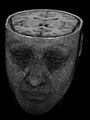

Ein Schnittbild gibt die inneren Strukturen so wieder, wie sie nach dem Aufschneiden des Objekts oder nach dem Herausschneiden einer dünnen Scheibe vorlägen. Man spricht hier von einer überlagerungsfreien Darstellung der entsprechenden Objektschicht – im Unterschied zu Projektionsverfahren wie etwa der gewöhnlichen Röntgenuntersuchung, bei der sich alle Strukturen überlagern, die im Strahlengang hintereinander liegen. Dieser Unterschied wird in der nebenstehenden Abbildung mit zwei tomografischen Schnittbildern (S1 und S2) und einem Projektionsbild (P) des gleichen Volumens illustriert.

Der Unterschied zwischen der überlagerungsfreien Darstellung in der medizinischen Tomografie und einer Projektionsabbildung ist in den nachfolgenden Abbildungen illustriert. In Projektionsverfahren wie der Radiografie (gewöhnliche Röntgenuntersuchung) wird ein Schattenbild aufgenommen, auf dem sich mehrere Strukturen überlagern, wenn sie im Strahlengang hintereinander liegen. Beispielsweise überlagern beim konventionellen Röntgenbild die Weichteile der vorderen und hinteren Brustwand und die knöchernen Strukturen des Thorax die Lungenstrukturen. Dies würde die Diagnose eines Lungentumors (z. B. Bronchialkarzinom) erschweren. Jedes CT- oder MRT-Schnittbild vom Thorax zeigt dagegen nur eine 0,5 bis 10 mm dicke Schicht, die praktisch überlagerungsfrei ist.

Röntgenbild (Projektionsbild) eines kleinen peripheren Bronchialkarzinoms im linken Oberlappen -